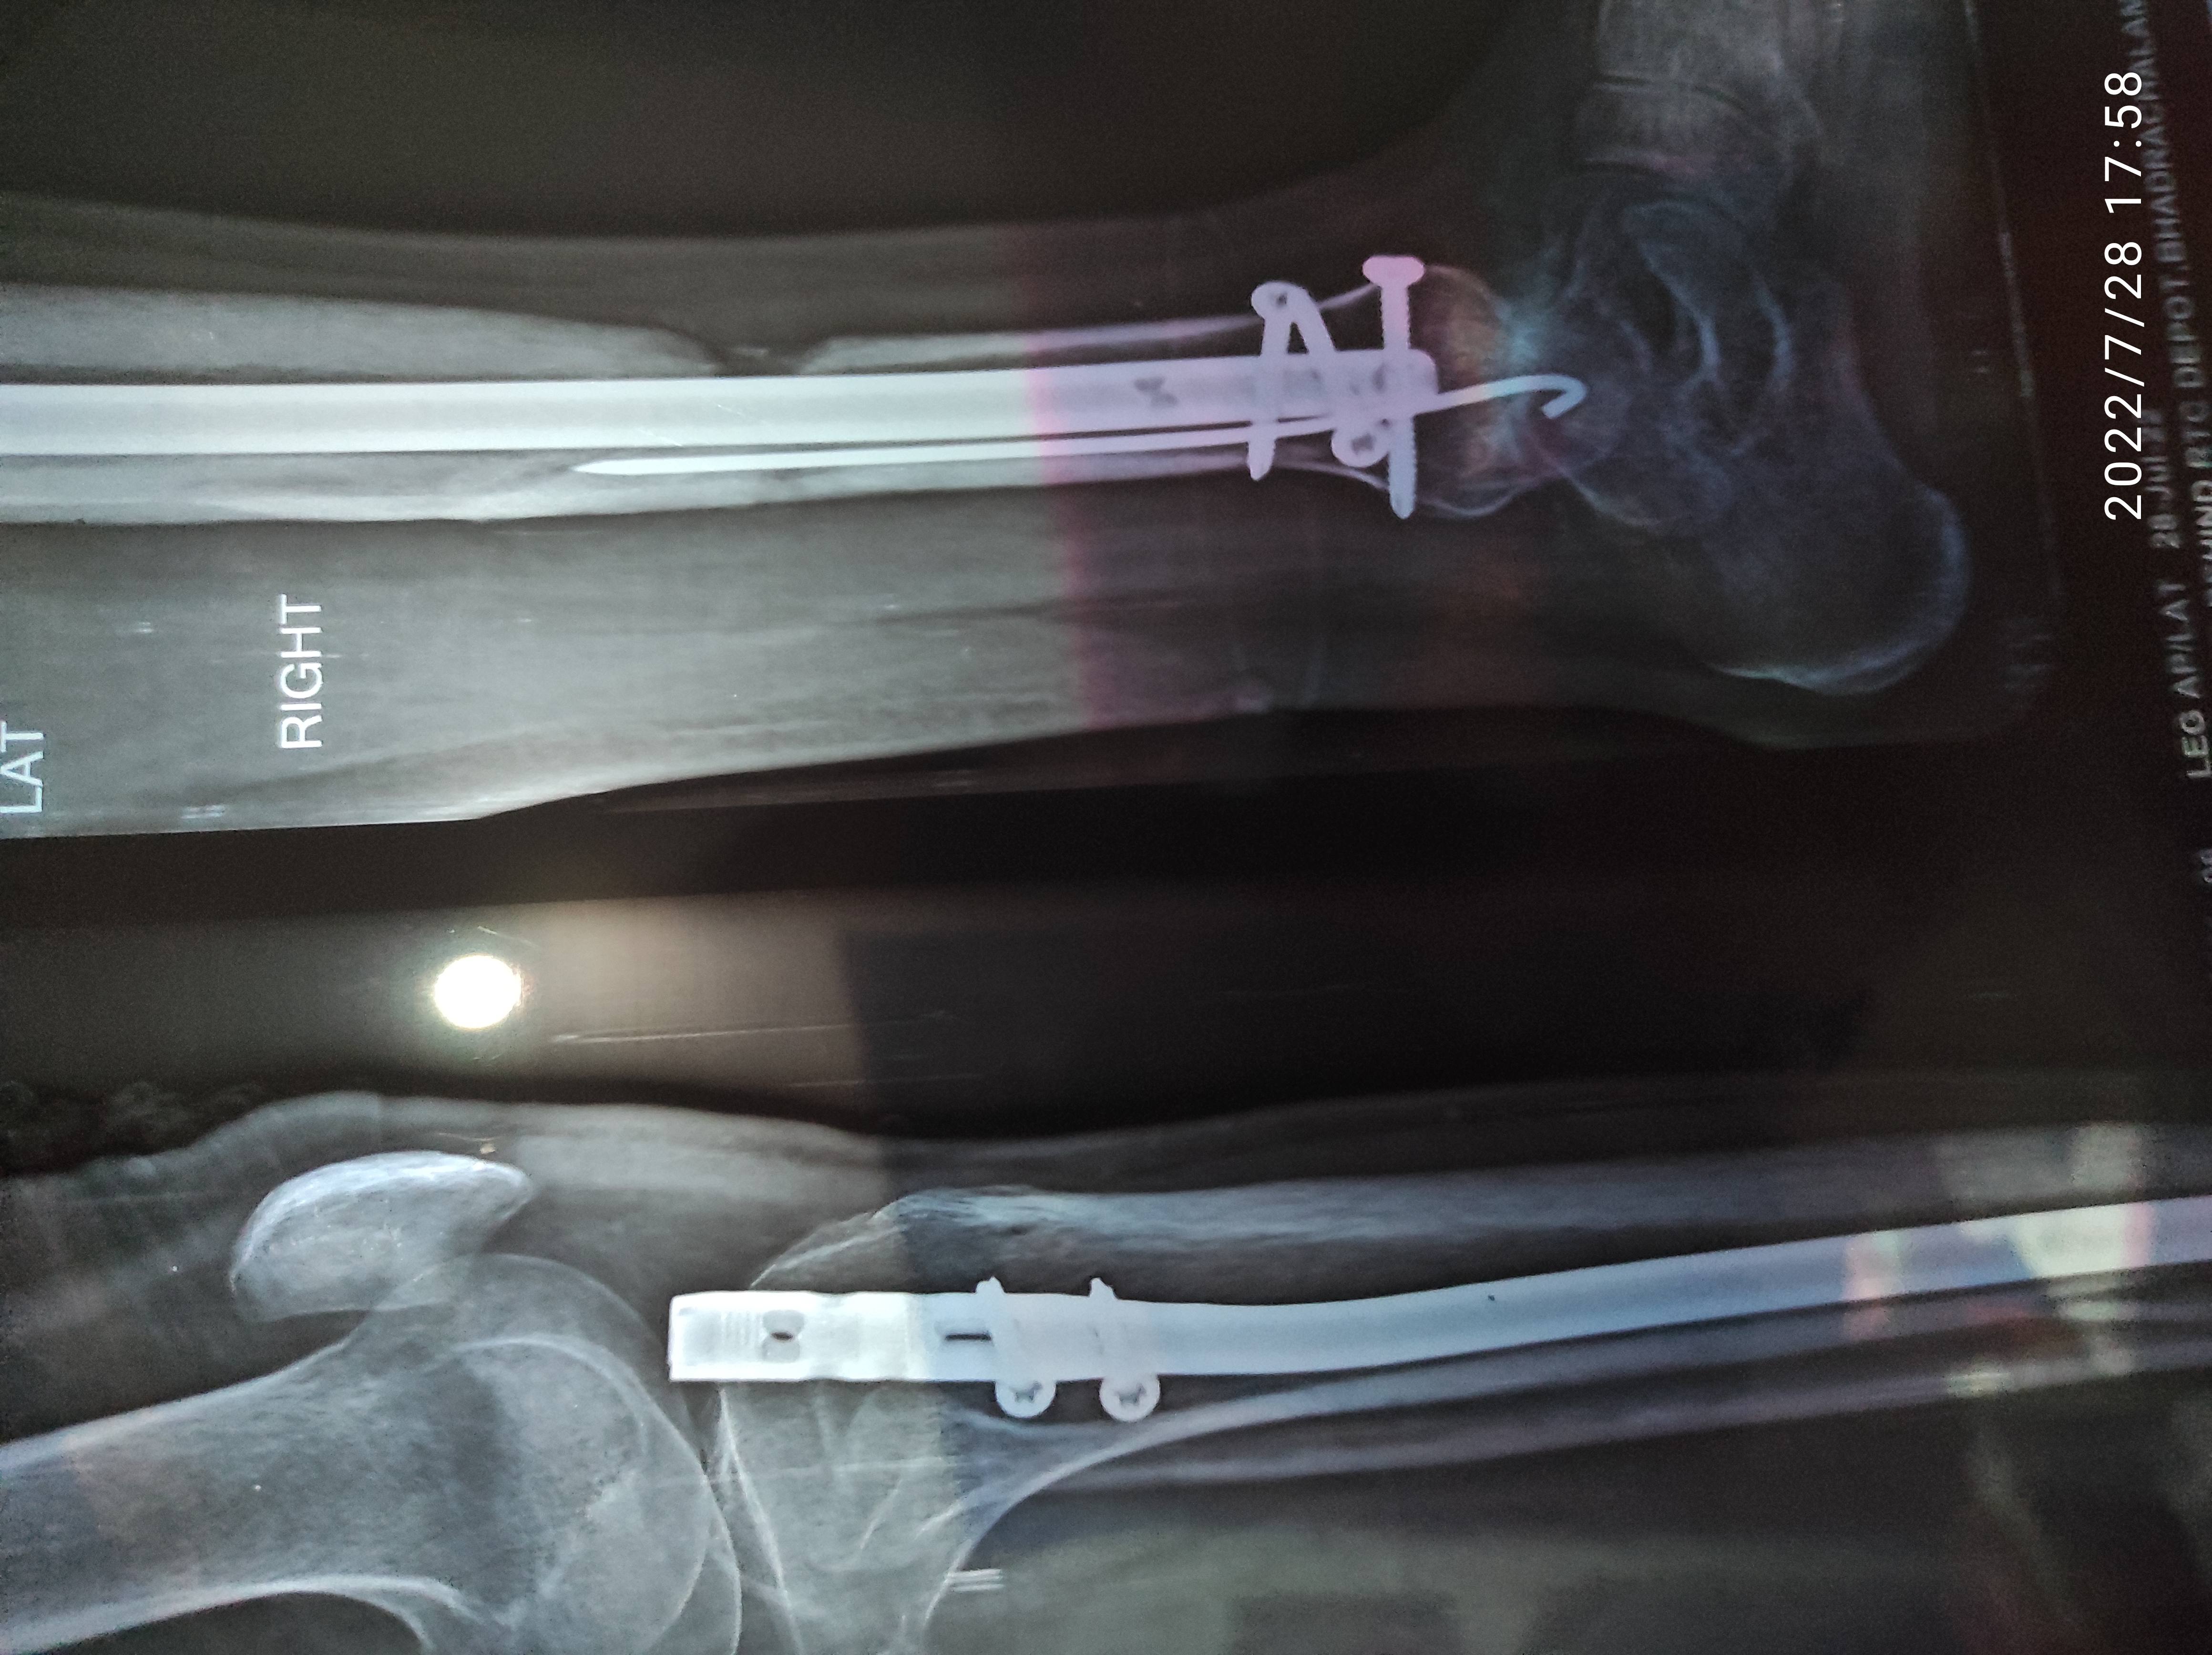

Fracture - COMMUNITED FRACTURE DISTAL 1/3RD TIBIA AND FIBULA

OPEN REDUCTION + INTERNAL FIXATION IM NAILING TIBIA (9X 345 MM,SYNTHES, TITANIUM) DONE UNDER SPINAL ANAESTHESIA ON 04/01/2022.

RIGHT SIDE

Surgery ke nearly 11 months ho chuke hai sir mere ghutne mai Rod chubhta hai aur kabhi kabhar dard hota hai limping hota hai thoda thoda aur bone bhi sayad nahi Jud raha hai..!

Kya mujhe bone grafting aur exchange nailing karwaleni chahiye plz bataaiye sir ??.?